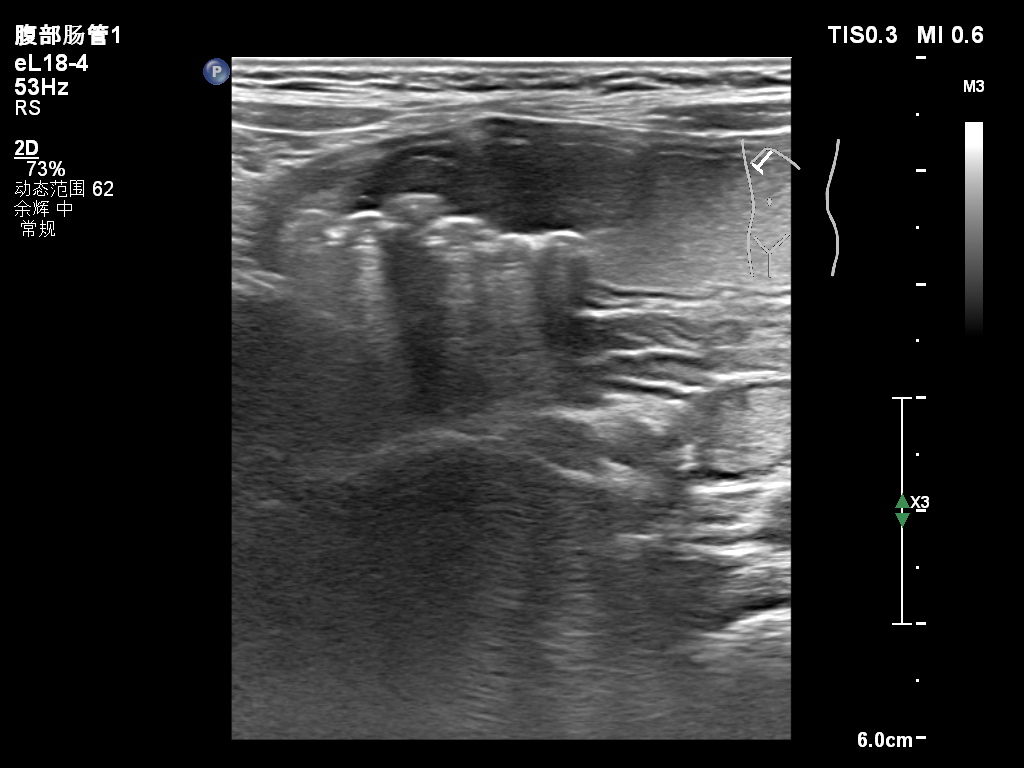

胃息肉